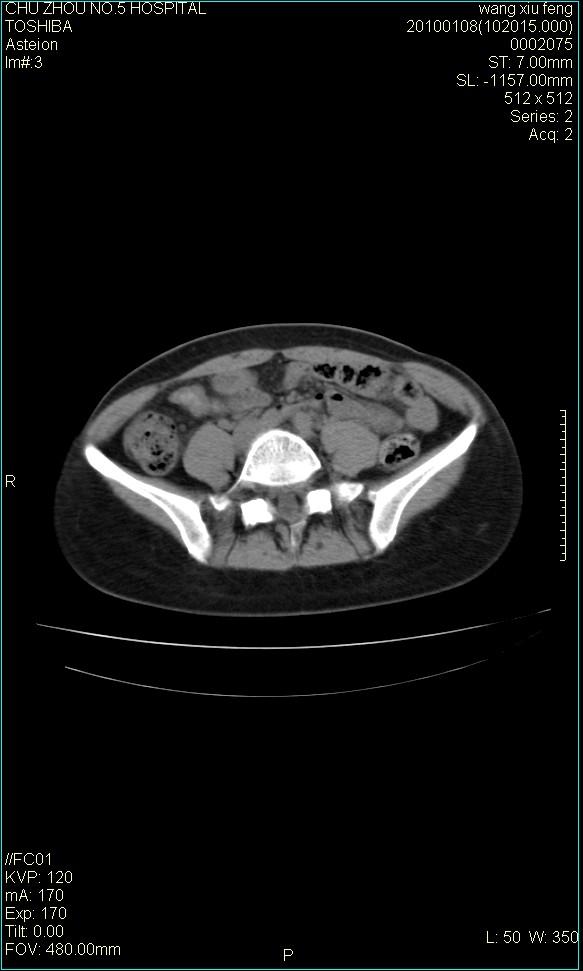

标题: CT24042:子宫右上方囊性包块,性质???? [打印本页]

标题: CT24042:子宫右上方囊性包块,性质????

f-41,左乳腺ca术后4年,b超示:子宫右上方囊性包块约5.5*3.4cm,前日行胸部ct平扫未见明显异常。

考虑右侧卵巢囊腺瘤?

右侧卵巢囊肿或小囊腺瘤。